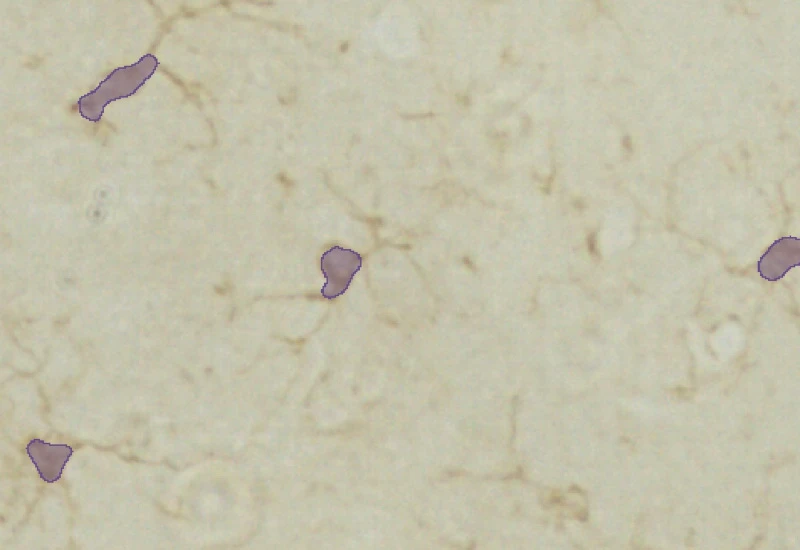

Original Image

Soma detection